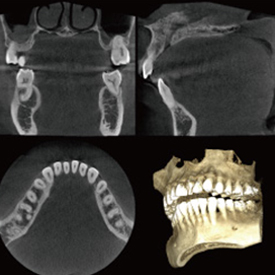

スマイルデンタルクリニックでは、歯科用CTを導入しているため、親知らずの形態、神経の位置を立体的に把握したうえで処置を行うことができます。

CTとはComputer Tomograghyの略で、日本語ではコンピューター断層撮影と訳されます。

これは、X線とコンピューターによって、歯や骨の位置や形態などを3D画像で立体的に撮影するための医療機器です。